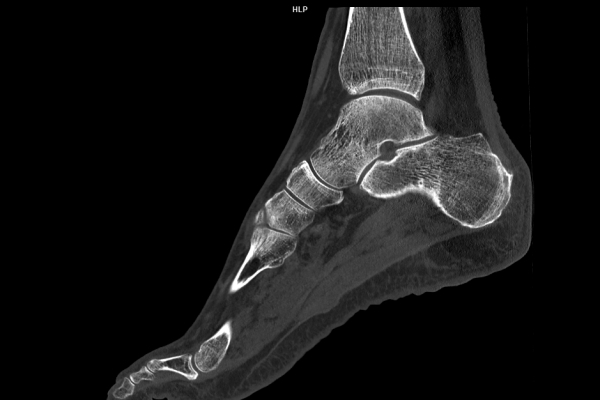

CT Untersuchung Bild

Modernste Bildgebung für jeden Bereich Ihres Körpers

Entdecken Sie, welche CT- und MRT-Untersuchungen in unserer Radiologie für jeden Bereich Ihres Körpers möglich sind.

• Muskuloskelettale Bildgebung

Wir bieten ein breites Spektrum an Untersuchungen an, von Standarduntersuchungen der Gelenke, Organe oder großflächigen Körperregionen bis zu Spezialuntersuchungen zum Beispiel des Herzen oder der Gefäße. Zusätzlich werden Angiographien (Darstellung von Blutgefäßen), Endometriose-Abklärungen und Mamma-Untersuchungen durchgeführt. Genauere Details können Sie der MRT/CT-Übersicht und der Preisliste entnehmen, oder Sie wenden sich direkt an unser Team, das Sie gerne zur passenden Untersuchung berät.

Die MRT (Magnetresonanztomographie) arbeitet mit Magnetfeldern und Radiowellen und eignet sich besonders für Untersuchungen der Weichteile wie Gehirn, Muskeln oder Gelenke. Die CT (Computertomographie) nutzt Röntgenstrahlen und liefert schnelle, hochauflösende Bilder, insbesondere für Knochen, Lunge oder innere Organe. Die Wahl der jeweiligen Untersuchung richtet sich an das individuelle Krankheitsbild und wird bei der Überweisung festgelegt.